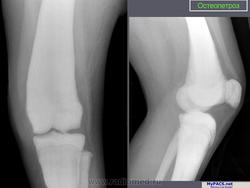

Морфологические изменения при остеопетрозе объясняются недостаточной активностью остеокластов. Макроскопически видно, что кости теряют костномозговой канал, концы длинных костей приобретают грушевидную форму (колбовидная деформация). Невральные отверстия становятся маленькими и сдавливают выходящие нервы. Первичная спонгиоза, которая удаляется в ходе начального роста, остается и заполняет полость костномозгового канала. Она не оставляет места для кроветворной части костного мозга и препятствует формированию зрелых костных балок. Формирующаяся кость не восстанавливает естественные структуры и имеет тенденцию к сохранению в грубоволокнистом состоянии. В конечном итоге эти внутренние аномалии делают кость хрупкой. Гистологически существенных изменений в количестве остеокластов обнаружить не удается, их число может быть чуть увеличенным, нормальным или уменьшенным.

Лабораторная и инструментальная диагностика. Характерны гипокальциемия, гипофосфатемия и повышение уровня ПТГ в сыворотке (вторичный гиперпаратиреоз). Всасывание кальция в кишечнике усилено, но гипокальциемия тем не менее сохраняется, поскольку ПТГ не активирует остеокласты. При рентгенографии и денситометрии костей обнаруживают их равномерное уплотнение и увеличение костной массы; компактное и губчатое вещество имеют одинаковую плотность. При гистологическом исследовании биоптатов кости выявляются толстые прослойки неминерализованного органического матрикса, иногда встречаются признаки остеомаляции (рахита). Количество остеокластов нормальное или даже увеличенное, но они малоактивны.

Мраморная болезнь (болезнь Альберс-Шенберга) - семейный генерализованный остеосклероз, протекающий с лейкемической реакцией крови у детей, с анемией и лейкопенией у взрослых, нередко с атрофией зрительных нервов и глухотой. Характерны деформация мозгового и лицевого черепа, заращение придаточных полостей носа плотной бесструктурной костной тканью. Ввиду постепенного сужения отверстий в черепе и межпозвонковых отверстий могут возникать полиморфные проявления поражения периферической нервной системы как на черепном, так и на позвоночном уровнях. В позвонках костные балки губчатого вещества утолщены и уплотнены. В трубчатых костях отмечается сужение, а затем и исчезновение костномозговых полостей, эпифизы булавовидно утолщены и поперечно исчерчены, имеется склонность к патологическим переломам. Наследуется по аутосомно-рецессивному типу и тогда, проявляясь в фенотипе в первые годы жизни, быстро приводит к смерти, или же - по аутосомно-доминантному типу, проявляясь в 20-40-летнем возрасте. Описал болезнь в 1907 г. Н.Е. Albers-Schonberg.